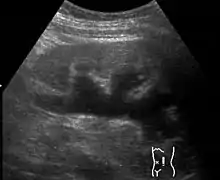

| Renal ultrasonography of hydronephrosis caused by a left ureteral stone. | |

Massive hydronephrosis as marked by the arrow.- Renal ultrasonography of hydronephrosis[14]